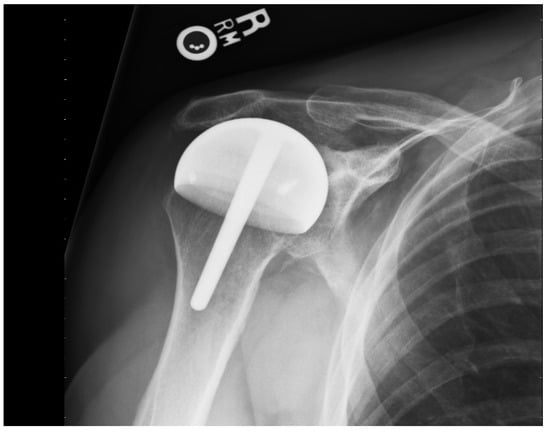

Titanium nitride (TiN) has high hardness and a low friction coefficient. It has been shown to be efficient in reducing the wear of cutting tools. It has been cleared by the Food and Drug Administration as an implant bearing surface and coating (510K 93122). It has much less wear compared to the cobalt chromium implants that are typically used for shoulder replacement and other resurfacing implants. In addition to reduced wear, there are no metal ions released into the tissues and, therefore, no chance of metal sensitivity or an allergic reaction [18,19,20]. The glenoid component, when needed, is either cemented or porous-backed polyethylene [10,15] (Figure 2).

Figure 2.

AP radiograph of a shoulder resurfacing with a polyethylene glenoid resurfacing component.